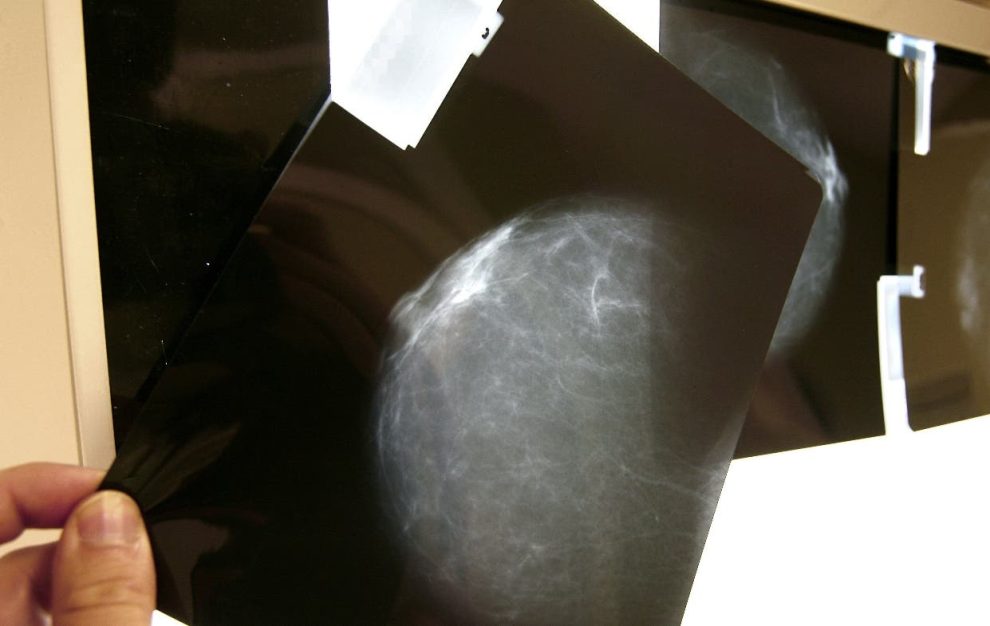

Se deben implementar servicios de mamografía en todas las regiones de República Dominicana, para realizar la mayor cantidad de pruebas posibles para detectar oportunamente el cáncer de mama. Así lo afirmó el doctor José Ramírez, director del Instituto Oncológico Rosa Emilia Tavares (INCART). Una mamografía no es un estudio perfecto, pero es algo que la humanidad debe detectar para detectar una enfermedad que afecta a casi 8,000 mujeres cada año en República Dominicana.

Considera que la inteligencia artificial autocorrige las mamografías.

“Toda mujer debería llevar un monograma cada año cuando cumpla 40 años”, afirma la experta. Recomiendo que la experiencia de la Primera Dama y del Servicio Nacional de Salud (SNS) en los 12 hospitales de la red se replique en todos los centros del país. Este experimento de detección se refiere al cáncer de mama, cuello uterino y próstata en hombres.

En República Dominicana, un alto porcentaje de mujeres ha oído hablar de la detección del cáncer de mama pero no lo hace o no tiene acceso, probablemente una cultura de la que solo hablamos en octubre, dijo la oncóloga. La docente enfatizó que el éxito de países como Uruguay ha estado en introducir la mamografía en la comunidad, para que el tamizaje llegue a las mujeres y no sean ellas las que tengan que ir a hacérselo. Se dice que el problema grave es la detección tardía, las mujeres deben consultar a un médico cuando no hay mucho más que hacer.